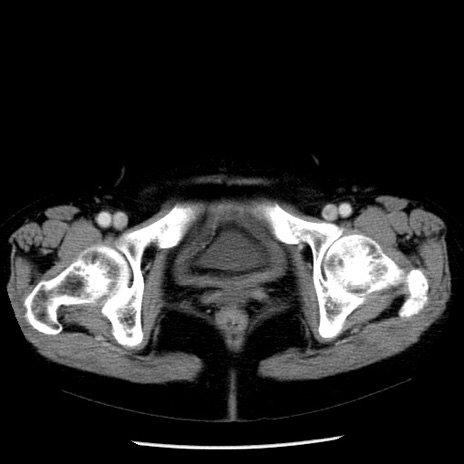

症例13(横断像)

【症例】70歳代女性

【主訴】腹痛、嘔吐

【現病歴】15時間程前(昨晩)より腹痛あり。今朝になっても症状の改善なく、嘔吐あり。腹痛も増悪あり、救急外来受診。

【既往歴】子宮癌全摘術後

【身体所見】意識清明、BP 121/72mmHg、P 74bpm、SpO2 100%(RA)、腹部:平坦・軟、腸雑音ほぼ聴取せず。下腹部・心窩部・臍左上に圧痛あり。反跳痛なし。

【データ】WBC 10600、CRP 0.15